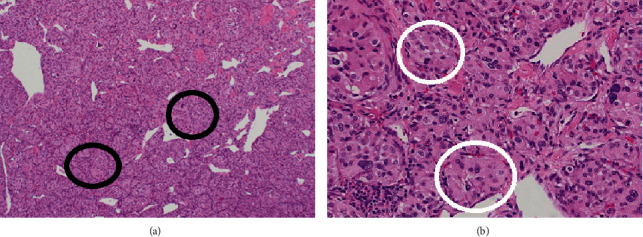

副神经节瘤是肾上腺外染色质细胞瘤。这些肿瘤中有一小部分可以在胸腔中发现,当在心脏中发现时,通常在左心房。在这个病例报告中,我们讨论了一个有SHDB突变的几个副神经节瘤病史的人,他在右心房发现了两个心脏副神经节瘤。

Paragangliomas are extra-adrenal chromaffin cell tumors. A small percentage of these tumors can be found in the thoracic cavity and, when in the heart, are typically in the left atrium. In this case report, we discuss the case of an individual with a history of several paragangliomas with the SHDB mutation who was found to have two cardiac paragangliomas in the right atrium.